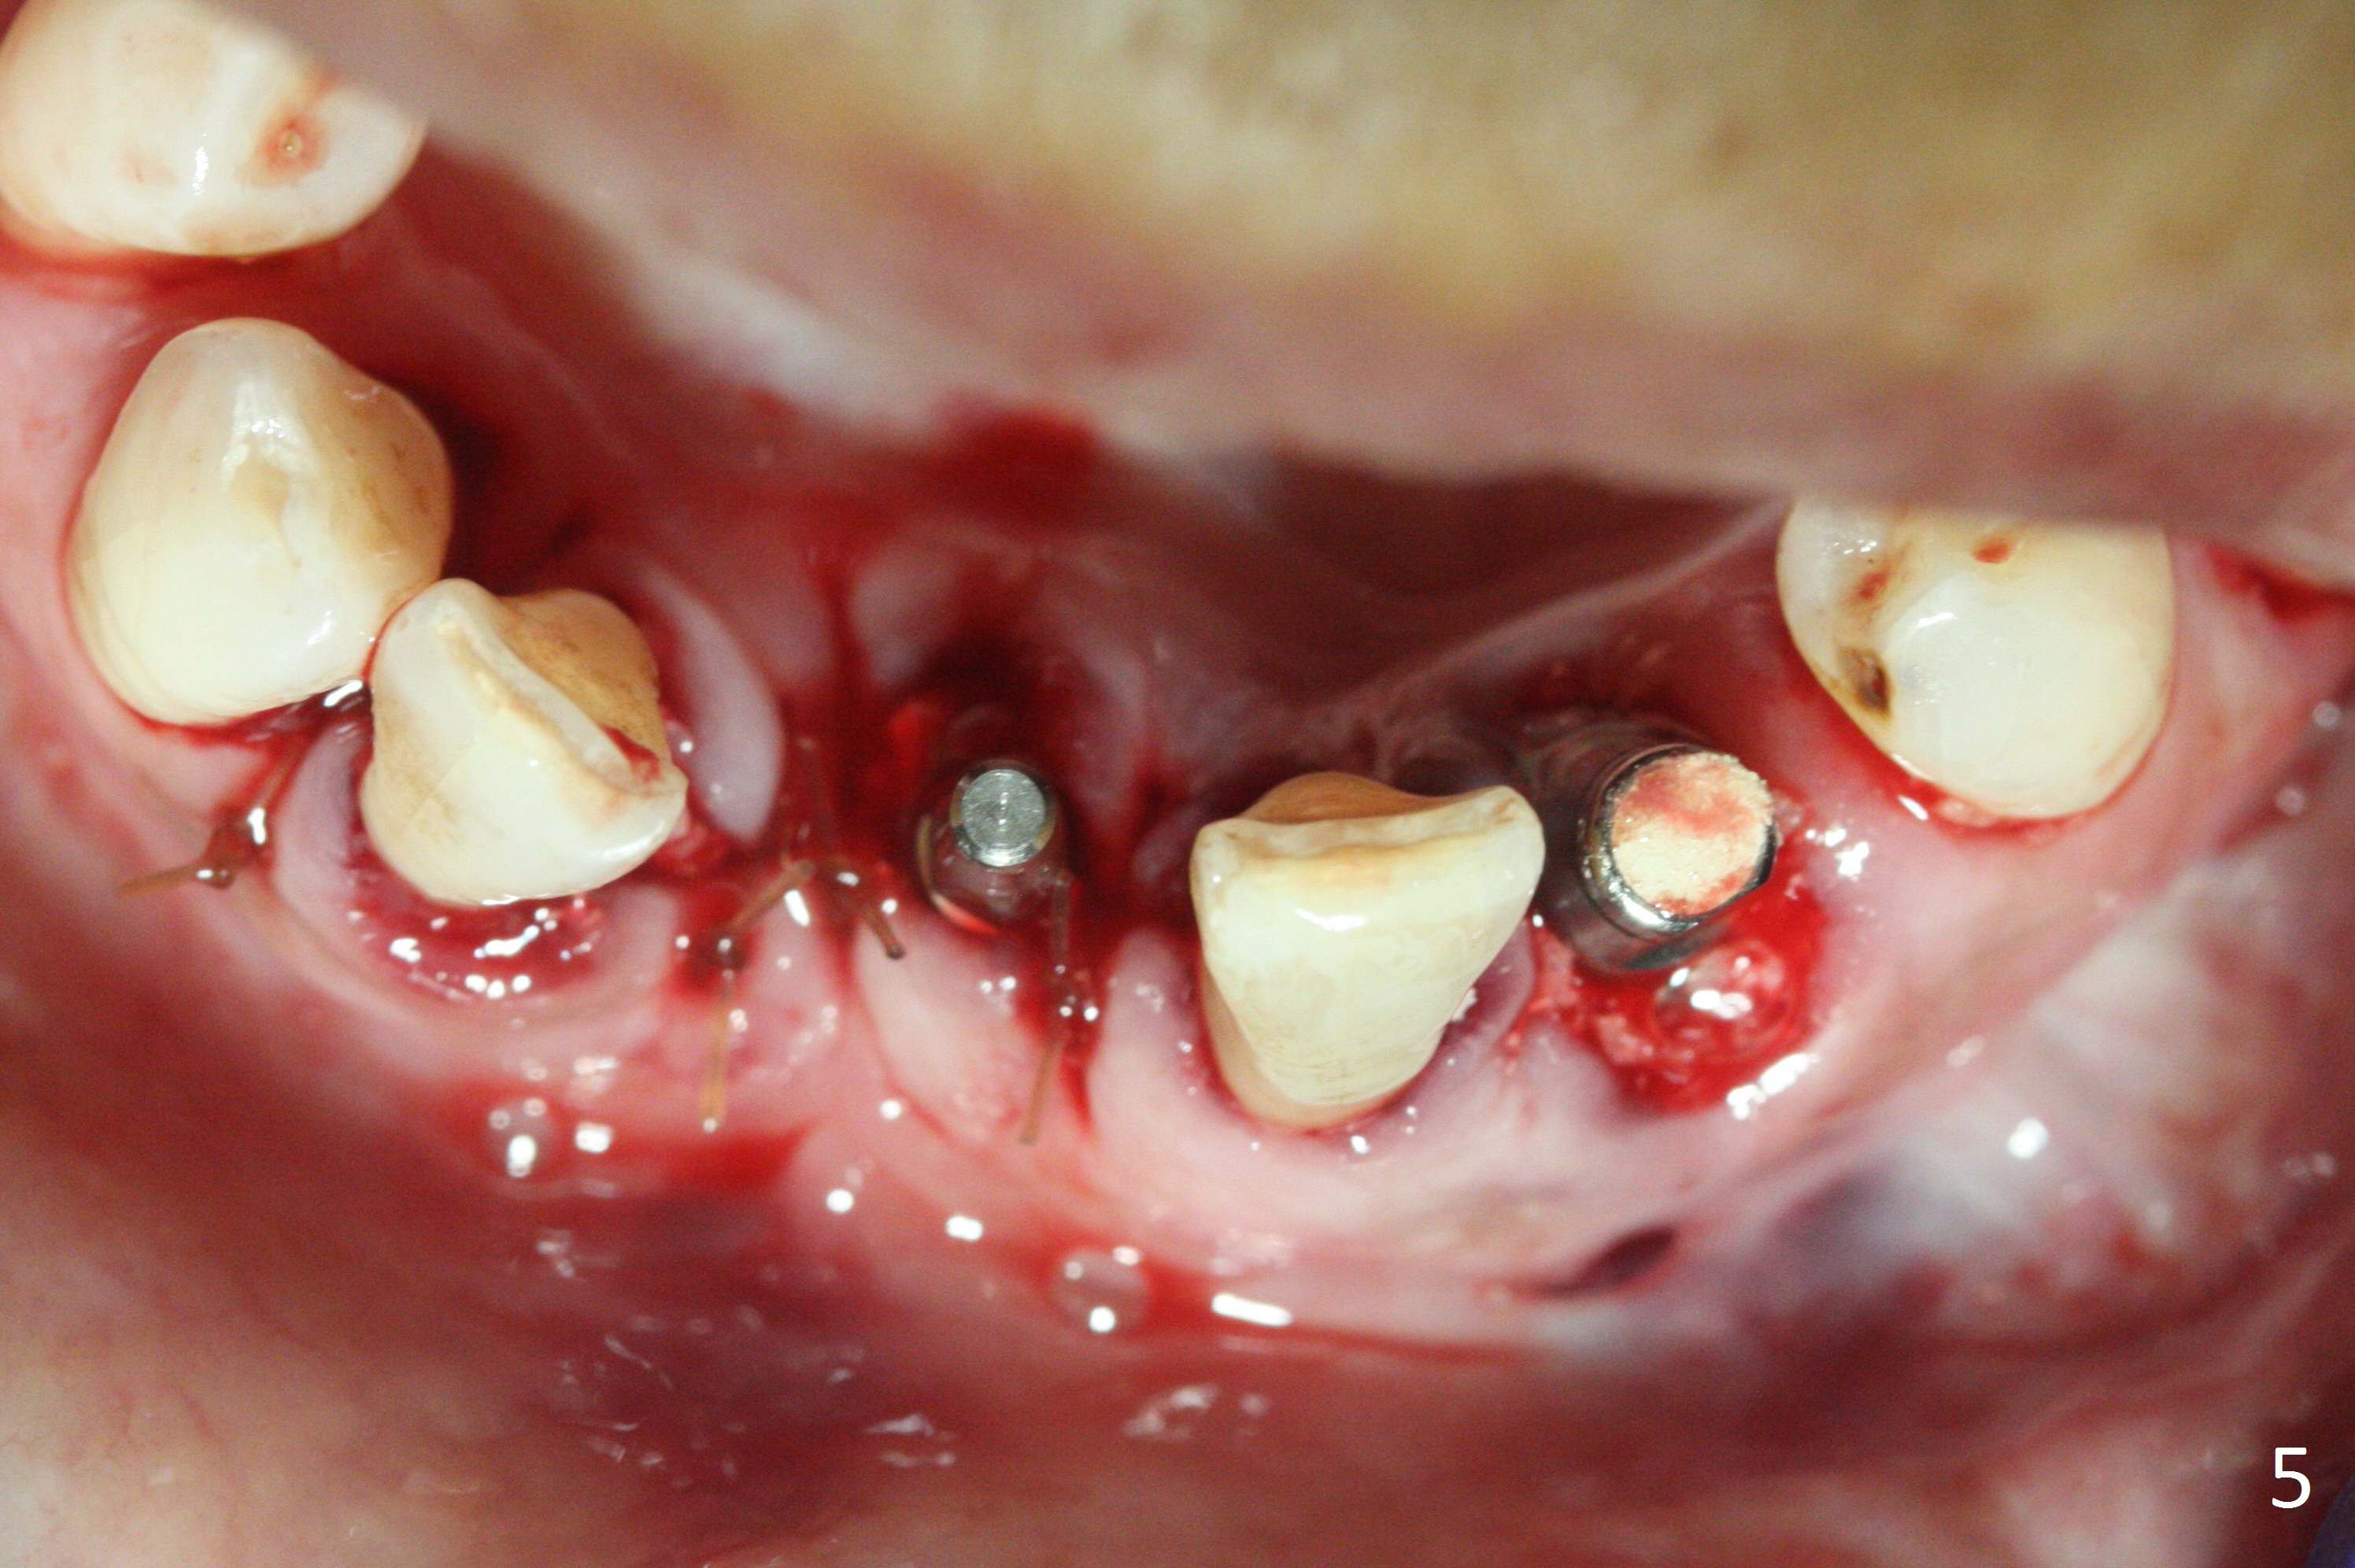

Before surgery, the patient reports that the tooth #25 has inclined to the position of #24 since the latter was extracted (Fig.1). After extraction of the tooth #25, there seems to be more bone vertically at the site of #24 than that of #25. Therefore the osteotomy is initiated at #24. The edentulous space is 9 mm mesiodistally, whereas the incisor width is 6 mm. The first pilot drill is fractured (1.2 mm). The latter is retrieved with incision. With better visibility, the initial osteotomy is found buccal. When a 3x14(2) mm dummy 1-piece implant is being placed partially, the buccal plate seems to be thin. A 2.5x14(4) mm 1-piece implant is placed instead with stability (Fig.2).

The depth of the osteotomy at #22 is 2-3 mm more than the expected implant length (Fig.2 with 2.7 mm drill in place). The implant at #22 (3.8x18 mm with insertion torque more than 50 Ncm) has clearance from the Incisive Canal and Mental Loop (Fig.3 red dashed line). Allograft with Osteogen is placed around the implants (Fig.4 *) in addition to Osteogen plug (cut in a thin layer) placed against the buccal wall of the socket at #22 (potential leakage). After suturing (Fig.5) and provisional cementation (Fig.6), periodontal dressing is applied (Fig.7). The implants seem to be ready for impression 4 months postop (Fig.8).